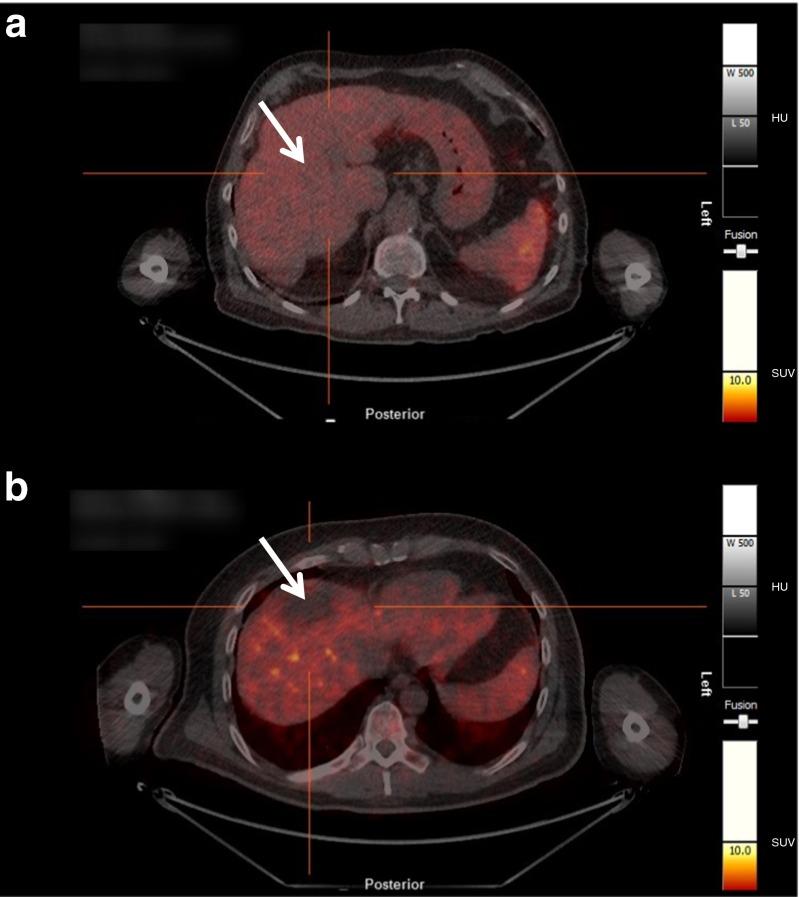

This study was designed to determine safety, tolerability, and radiation burden of a [(68)Ga]NODAGA-RGD-PET for imaging integrin αvβ3 expression in patients with hepatocellular carcinoma (HCC) and liver cirrhosis. Moreover, metabolic stability and biokinetic data were compiled.

The radiopharmaceutical was well tolerated and no drug-related adverse effects were observed. No metabolites could be detected in blood (30 and 60 min p.i.) and urine (60 min p.i.). [(68)Ga]NODAGA-RGD showed rapid and predominantly renal elimination. Background radioactivity in blood, intestine, lung, and muscle tissue was low (%ID/l 60 min p.i. was 0.56 ± 0.43, 0.54 ± 0.39, 0.22 ± 0.05, and 0.16 ± 0.8, respectively). The calculated effective dose was 21.5 ± 5.4 μSv/MBq, and the highest absorbed radiation dose was found for the urinary bladder wall (0.26 ± 0.09 mSv/MBq). No increased uptake of the tracer was found in HCC compared with the background liver tissue.

[(68)Ga]NODAGA-RGD uptake in the HCCs lesions was not sufficient to use this tracer for imaging these tumors. [(68)Ga]NODAGA-RGD was well tolerated and metabolically stable. Due to rapid renal excretion, background radioactivity was low in most of the body, resulting in low radiation burden and indicating the potential of [(68)Ga]NODAGA-RGD PET for non-invasive determination of integrin αvβ3 expression.